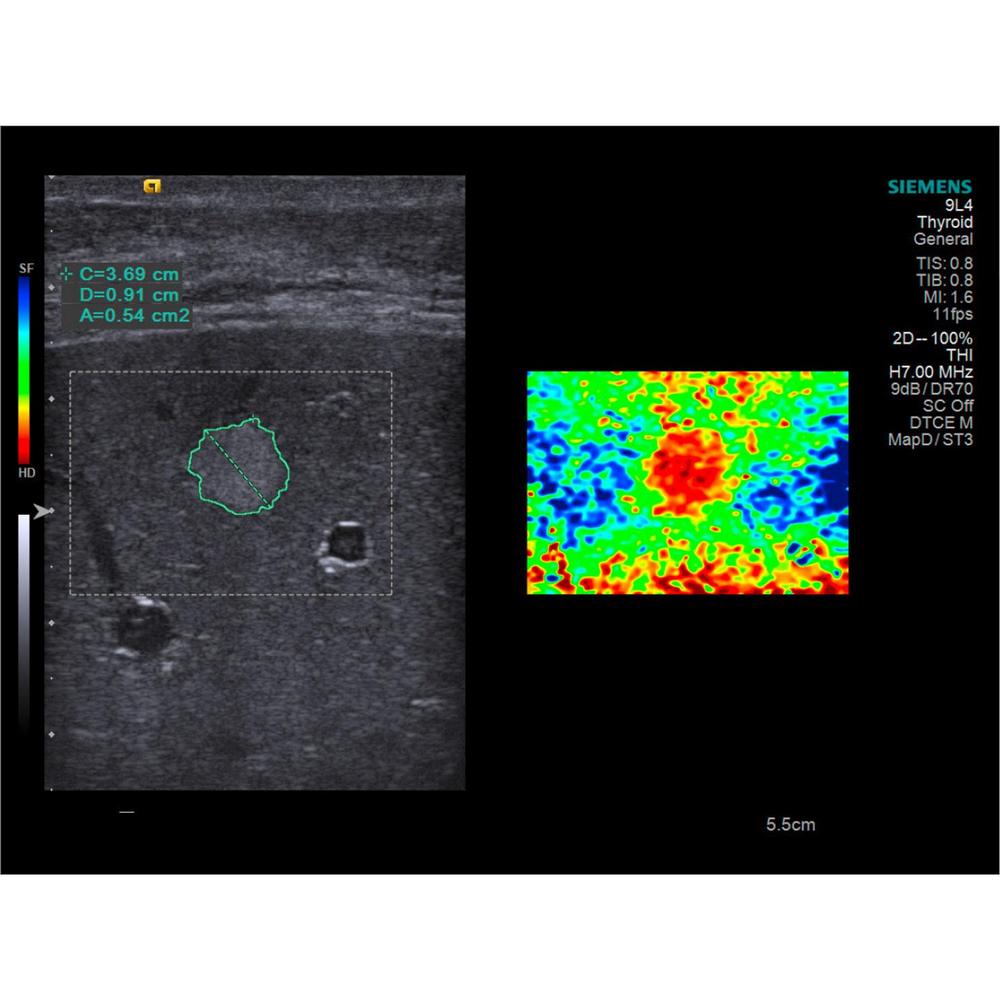

Оценка жесткости тканей с помощью эластографии на основе анализа сдвиговой волны

- Приложение Virtual Touch™ компании Siemens, основанное на технологии визуализации с усиленным акустическим импульсом (Acoustic Radiation Force Impulse, ARFI), открывает совершенно новые возможности для получения диагностической информации.

- Качественную оценку изображений или результаты количественных измерений скорости прохождения сдвиговой волны можно получать с помощью конвексных, линейных и других датчиков в целом ряде диагностических исследований.

• Возможность эластографии.

| Компрессионная эластография | Да |

| Вид эластографии | Компрессионная |